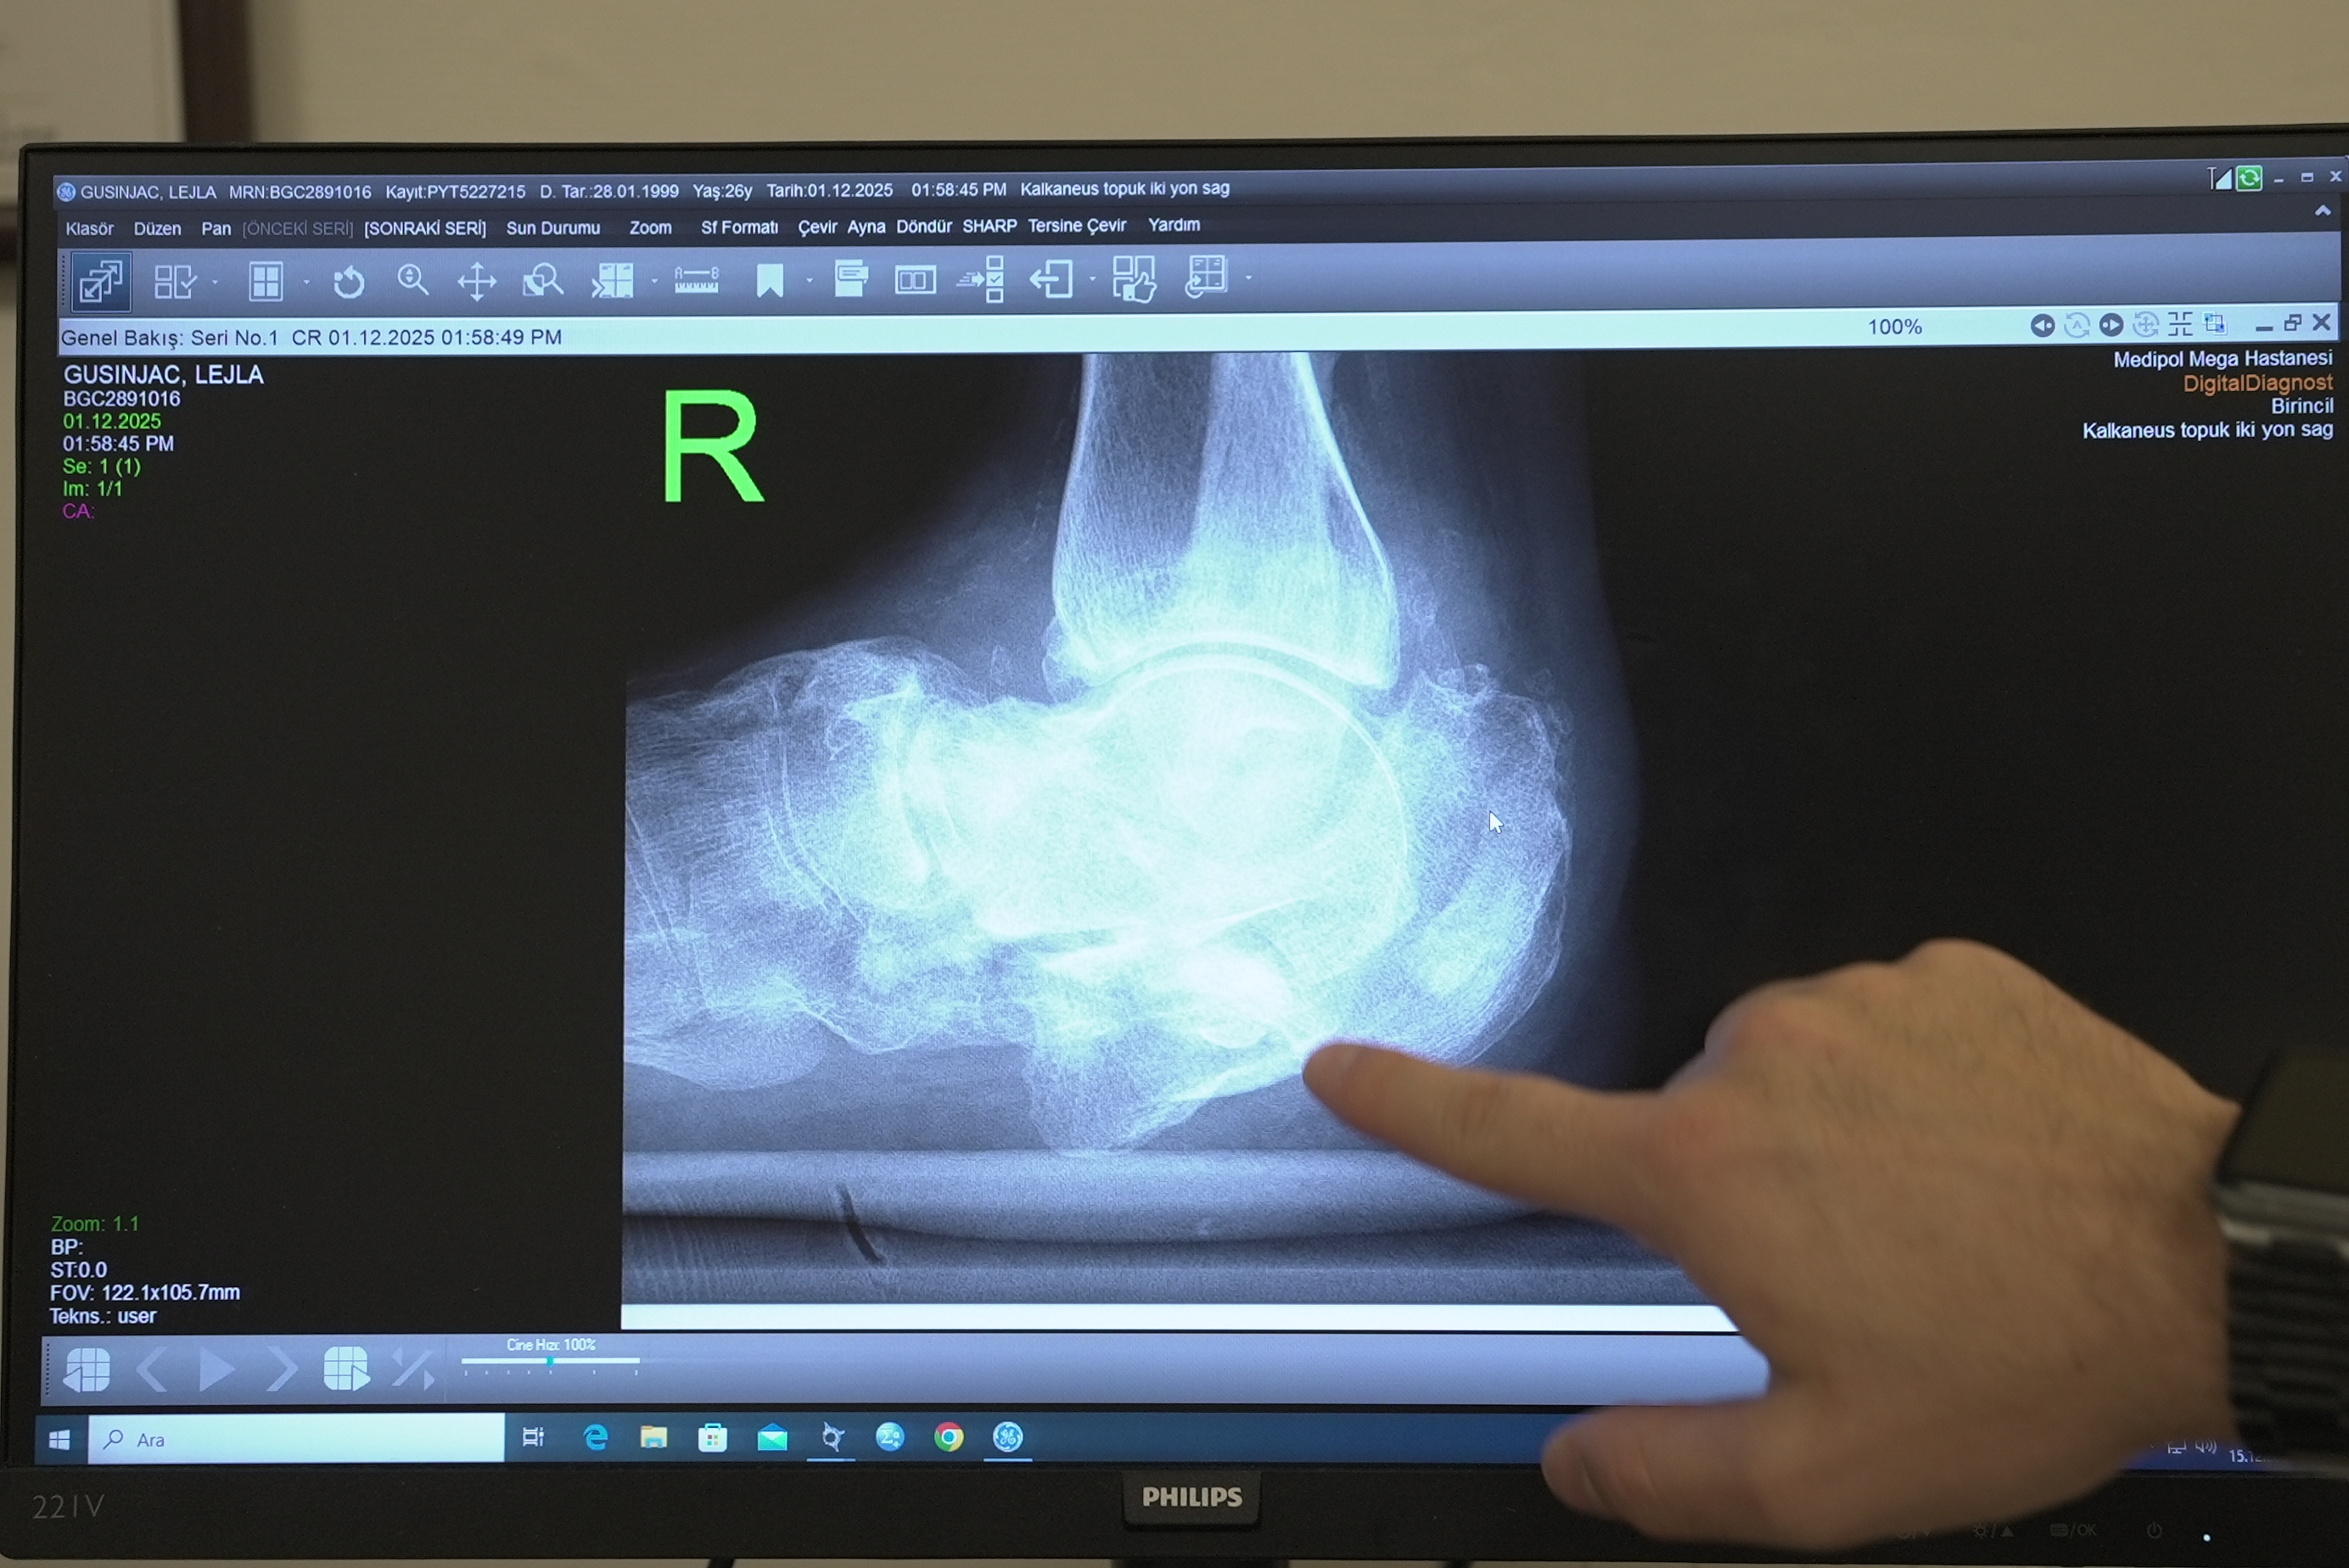

Diyabetle gelen sağlık sorunlarına değinen Doç. Dr. Çatal, “Hastamız 26 yaşında ve uzun yıllardır kontrolsüz diyabeti bulunuyor. Diyabet hastalarında ayaklarda his kaybı oluşabiliyor. Bu nedenle küçük bir kırık bile fark edilmeden ilerleyerek ciddi deformasyonlara yol açabiliyor. Hastamızda topuk kemiğinde, yani kalkaneus dediğimiz kemikte ciddi bir kırık gelişmiş. Üzerine basmaya devam ettikçe ayağında genişleme oluşmuş. Ameliyatta topuk kemiğini yeniden yapılandırdık. Kalça kemiğinden aldığımız kemik greftleriyle bir ‘kurtarma cerrahisi’ uyguladık. Amacımız, hastanın ağrısız ve düzgün basabileceği, normale en yakın anatomiyi sağlamaktı. Bu hedefe ulaştık.” diye konuştu.

Tedavi sürecini anlatan Lejla Gusinjac, “İki yıl önce merdivenlerden düştüm. Ayağımda kırıklar oluştu ama ne kadar ciddi olduğunu fark edemedim. Ülkemde yapılan tetkiklerde de kırığın boyutu anlaşılamadı. Zamanla bana ayağımın çürüdüğü, kemik kalmadığı ve dizime kadar kesilmesi gerektiği söylendi. O an hayatımın bittiğini düşündüm. Annem ve arkadaşım Medipol’ü duydular. Tüm belgelerimi gönderdik. Gelen yanıtla yüzümdeki gülümseme geri geldi. İlk kez biri bana ayağımın bir çözümü olduğunu söyledi”

Tedavinin her aşamasında bilgilendirildiğini söyleyen Gusinjac, ameliyat sonrası yaşadığı duyguyu şu sözlerle dile getirdi: “Doktorum bana adım adım ne yapılacağını anlattı ve güven verdi. Ameliyatta belimden alınan kemik ayağıma yerleştirildi. Kaynama başladığını duyduğum anı asla unutamam. Ayağımı kurtardığınızı öğrendiğim an, hayatım yeniden başladı. Siz bana sadece ayağımı değil, umudumu ve hayatımı geri verdiniz. Medipol’e, doktoruma ve tüm ekibe minnettarım.”